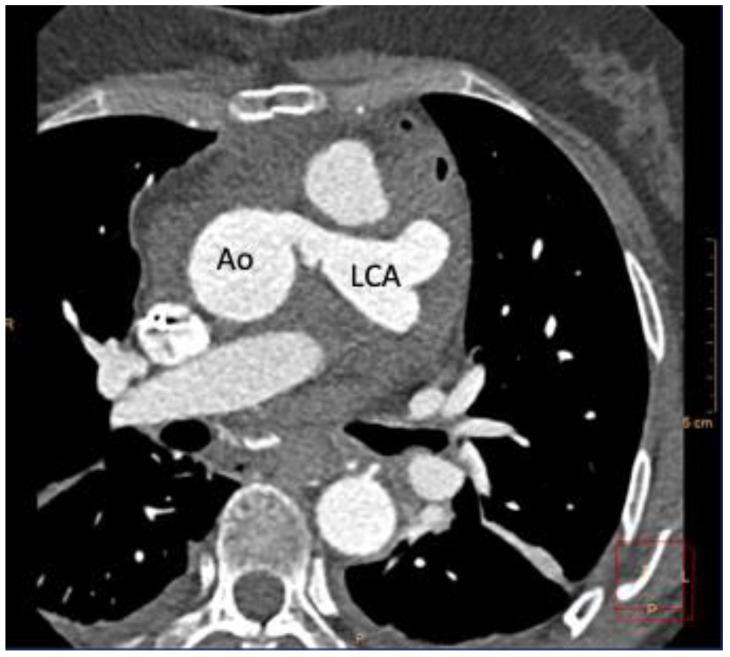

成人冠状动脉左前降支起源于肺动脉(ALCAPA)并发心搏骤停 1 例报告

Sudden Cardiac Arrest in an Adult with Anomalous Origin of the Left Coronary Artery from the Pulmonary Artery (ALCAPA): Case Report.

We report a rare case of resuscitated sudden cardiac arrest in a 55-year-old female, who was diagnosed with ALCAPA and underwent successful surgical correction and implantable cardioverter defibrillator (ICD) implantation for secondary prevention.

我们报告了一例罕见的 55 岁女性复苏性心搏骤停病例,该患者被诊断为 ALCAPA,并接受了成功的手术矫正和植入式心律转复除颤器(ICD)植入术以进行二级预防。